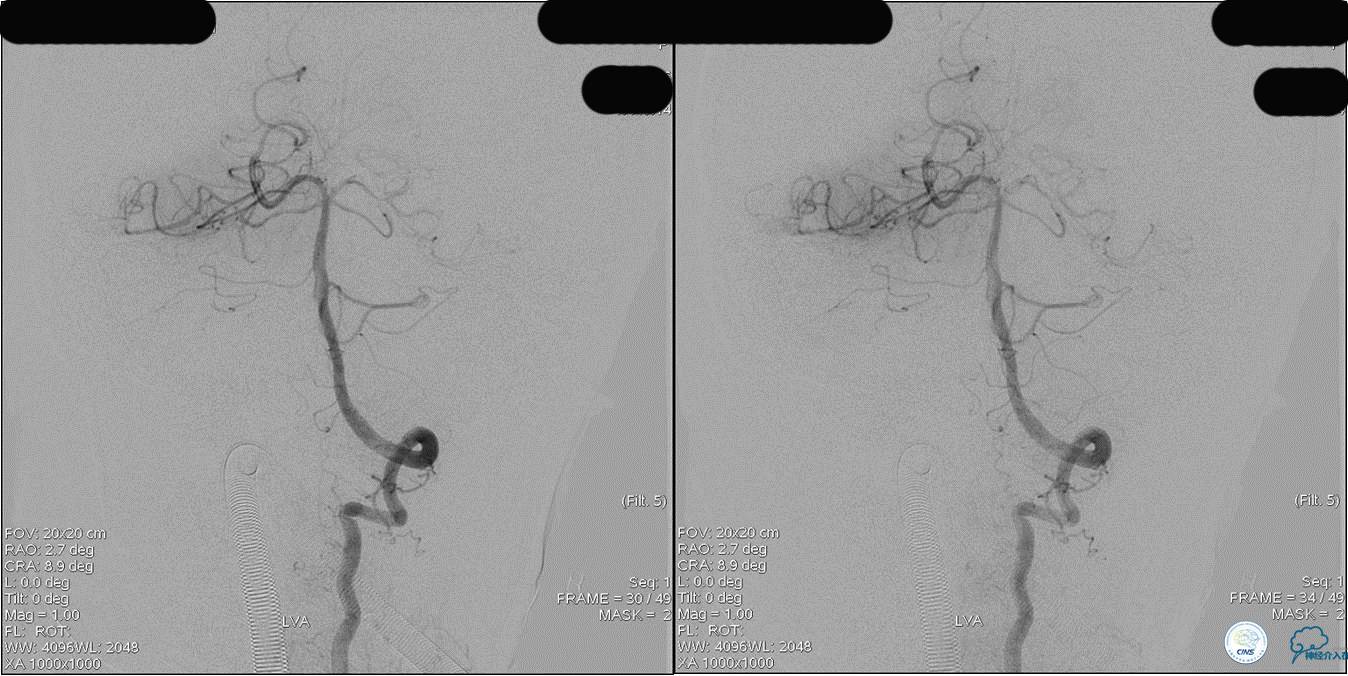

》DSA资料(第3次取栓后,发病10h)

》DSA资料(观察30min后,左椎造影)

术后